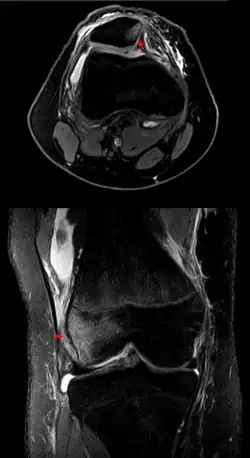

Zwichnięcie rzepki – przemieszczenie rzepki, w którym wypada ona z bruzdy międzykłykciowej. Najczęściej rzepka ulega zwichnięciu do boku.

- Hipoplazja kłykcia bocznego kości udowej